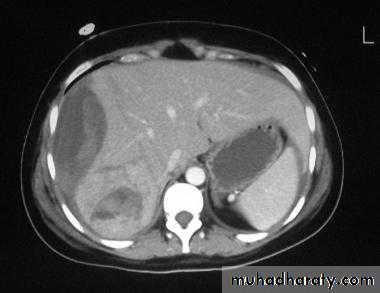

CT is more sensitive and specific. Lacerations and hematomas are recognized as low density areas relative to the normal intact, enhanced parenchyma. Leakage of contrast indicate active bleeding

Fatty infiltration of the liver

It is a frequent finding, particularly in those with hypercholesterolaemia, obesity, diabetes or those who take alcohol to excess. It may involve the whole liver or it may just involve individual subsections

At CT, liver density is less than splenic density

At US, increased liver echogenicity (bright liver)MRI useful in problem cases because fat gives a characteristic set of signals